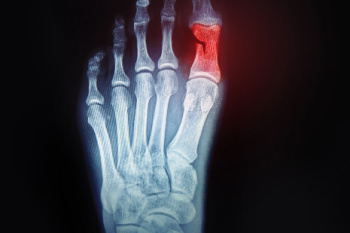

A broken toe is a fracture of one of the small bones in the toe, often caused by direct trauma or excessive force. This injury may occur from stubbing the toe, dropping a heavy object on the foot, or experiencing a sports-related accident. Common symptoms include sharp pain, swelling, bruising, tenderness, and difficulty walking. In some cases, the toe may appear misaligned or feel stiff. Diagnosis is typically made through a physical examination and confirmed with an X-ray to determine the extent of the fracture. A podiatrist can provide proper treatment, stabilization, and guidance for healing. If you have sustained a toe injury, it is suggested that you consult a podiatrist who can provide an accurate diagnosis and effective treatment solutions.

A broken toe occurs when one or more of the toe bones of the foot are broken after an injury. Injuries such as stubbing your toe or dropping a heavy object on it may cause a toe fracture.

Although the injured toe should be monitored daily, it is especially important to have a podiatrist look at your toe if you have severe symptoms. Some of these symptoms include worsening or new pain that is not relieved with medication, sores, redness, or open wounds near the toe.